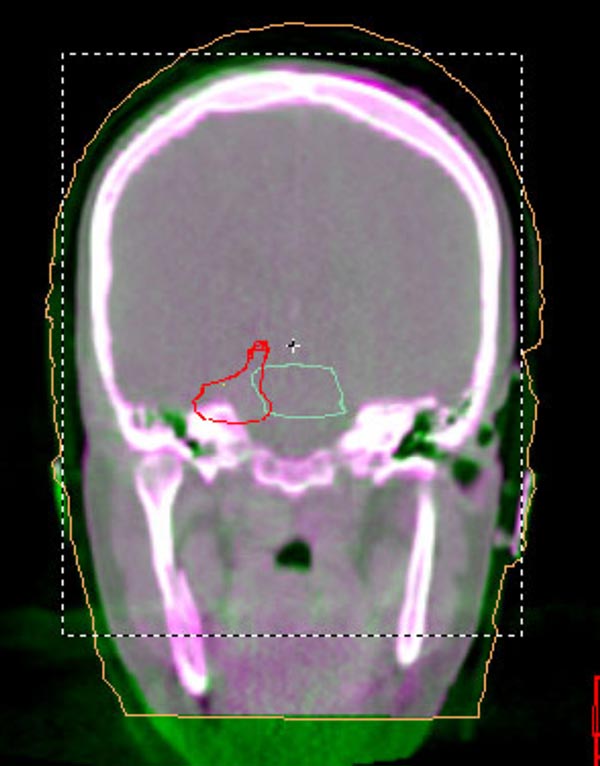

We understand that a cancer diagnosis can be scary, which is why Florida Center For Prostate Care is dedicated to compassionate care and state-of-the-art technology. Florida Center For Prostate Care uses the Elekta Synergy® machine, a digital accelerator for advanced image-guided radiation therapy (IGRT). It is the only all-digital treatment device in the world. This allows your doctor to view your tumor in real-time at the time of your treatment.

The 3-D high-quality images taken at the time of your treatment can be studied against your previous CT scans precisely and promptly to ensure that the doctors are treating your tumor as accurately as possible while greatly limiting any exposure to healthy tissue in the area.

Elekta Synergy® provides unparalleled clinical assurance to more aggressively treat tumors while keeping damage to surrounding healthy tissues to a minimum. Elekta Synergy®‘s precision accuracy reduces or eliminates the use of markers because clinicians can view soft tissue using Elekta Synergy®‘s VolumeViewTM. The low-dose imaging proficiency helps minimize the side effects of radiation therapy by decreasing the margins previously set to account for the unpredictability of target location, movement, and dimensions.